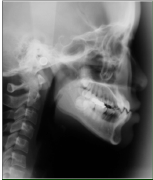

• レントゲンとセファロ分析

この検査をすることで、歯並びの原因が骨組みにあるのか、歯にあるのかが分かります。また、その治療をするために、成長が利用できるのかできないのか、どんな治療が必要か、その治療目的にはどの装置が最もよいのかを見極めなくてはなりません。

検査結果がすべて出揃いましたら、そこではじめて診断ができます。ここで、現在どんな問題が起きているのか、何を治したらよいのか、目標はどこに置くのか、またそのために歯を抜くのかどうかはどんな装。